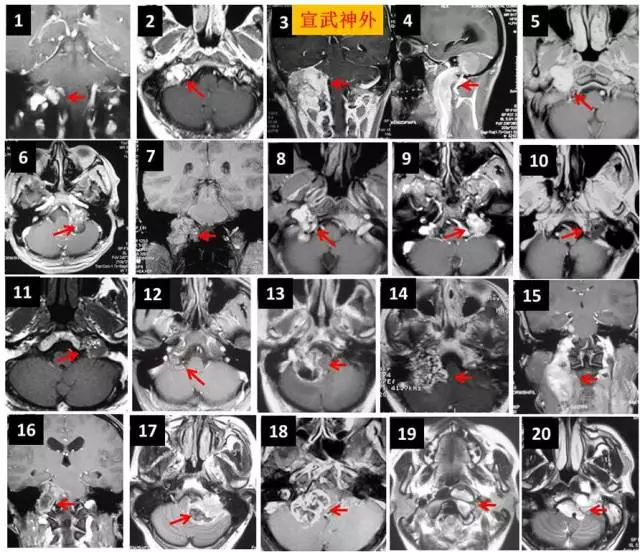

颅底疾病全覆盖

手术体位及入路

听神经瘤

手术体位个性化选择

嗅沟脑膜瘤

岩斜脑膜瘤

脑桥海绵状血管瘤

颈静脉孔区肿瘤

颈静脉孔内外沟通型神经鞘瘤

内镜经口+乙状窦后入路显微手术 分期手术

幕上下联合入路

颈静脉球瘤